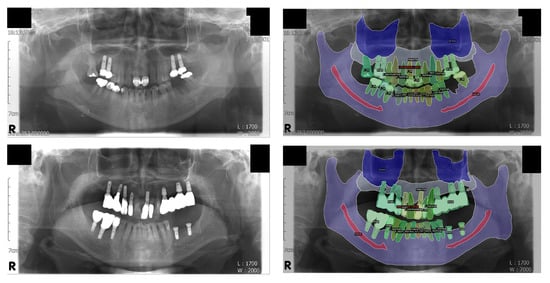

In order to visually examine the inference results, the output values of the model were visualized and superimposed on the original inputs of the panoramic radiographs (Figure 3).

Figure 3.

Visualization of the inference results. Some structures, including the mandibular canal and the medial wall of the maxillary sinus, are difficult to distinguish on the original panoramic radiographs but are fairly well segmented. Note that the normal tooth, treated tooth, and dental implant classes are individually segmented for each object; this was not possible with conventional semantic segmentation. Left: original input panoramic radiographs. Right: visualized result of the model’s inference.

The segmentation of the mandibular canal showed the lowest PQ and SQ among the “stuff” classes, which was consistent with the results of the IoU. However, as shown in Figure 3, most of the original input panoramic radiographs tested were faint, making it difficult to read and identify the mandibular canal. Moreover, as can be seen in the confusion matrix, the prior value of the mandibular canal was the lowest among all classes, which showed that the area covered by the mandibular canals was less than 2% of the entire pixels. Nevertheless, our model correctly detected almost 80% of the ground truth pixels of the mandibular canal. A previous study, which proposed the concept of panoptic segmentation, tried to compare the artificial neural networks to human annotators and showed that human annotators outperformed the machines [13]. Given that artificial intelligence has not surpassed humans in this task so far, the recognition of the mandibular canal in the current study might be considered as a meaningful achievement.

Among the stuff classes, the maxilla showed the second lowest evaluation score after the mandibular canal, which can be seen from the PQ and IoU results. The reason for this is presumed to be the unclear boundary between the maxillary sinus and maxilla; moreover, some structures, such as the hard palate and zygomatic arch, often interfere with the readings. There are cases where the central part of the maxilla is not clear because of the overlap of a ghost image caused by the cervical spine. In addition, the number of pixels in the area covered by the maxilla was the second smallest (<5%) after the number of pixels covered by the mandibular canal, among the stuff classes. Nonetheless, the model detected almost 90% of the ground truth pixels of the maxilla correctly, as can be seen in the confusion matrix. Surprisingly, the results for the maxillary sinus were even better (96% of the total ground truth pixels were accurately detected), considering the fact that the medial wall and the floor of the maxillary sinus are difficult to identify and interfere with other structures, such as the innominate line and nasal floor, in most cases. It is very important to determine the location and shape of the maxillary sinus and mandibular canal during dental implant surgery; therefore, these results suggest that artificial intelligence will be of great help in dental clinics in the future.